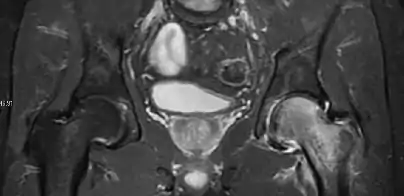

Magnetic resonance imaging

Many pathological conditions of the hip are detected early by MRI due to its high soft tissue resolution and sensitivity. Its accuracy in studying acute hip pain in children has proved to be superior to ultrasound and plan film radiography. However, MRI accessibility and the need of sedation relegate its use to selected cases in which diagnosis is not clear with less demanding techniques. These include differentiating transient synovitis from a septic arthritis or osteomyelitis, diagnosis of inflammatory joint disease or bone tumors, and early detection and follow-up of Perthes disease.[1]

In adults, MRI is currently playing a definite role in the assessment of osteoarthritis. Although traditionally belonging to the arena of radiographs, the role of MRI has been stressed after the term femoral acetabular impingement was coined in 2003. Growing interest has been focused in accurate diagnosis of the acetabular and femoral morphological abnormalities that may lead to early osteoarthritis.[1]

MR imaging is considered paramount to these objectives, mainly when surgery is considered, due to the ability of MRI to portray the whole section of the femoral neck surface, as well as to image the labrum and articular cartilage.[1]

Most of the angles and measurements described in the plain radiograph section can be accurately reproduced on MRI. In addition, the superiority of MRI resolution with intra-articular contrast allows detection of labral and chondral abnormalities that may influence the choice of medical, percutaneous, or surgical management (Figure 9).[1]

Figure 9:

Sagittal T1 weighted image showing anterosuperior labral tear.[1]

Sagittal T1 weighted image showing chondral lesion.[1]